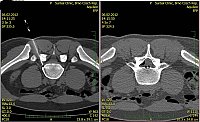

2. Muž, 41 let. Na MR objemná hernie L4/5 velikosti 11mm téměř vyplňující páteřní kanál, útlak nervových kořenů. Opakovaně doporučována operace, kterou pacient odmítl. Jako alternativu zvolil ozonoterapii s aplikací ozonu do disku L4/5 a periradikulárně. Byly aplikovány celkem 3 dávky ozonu. Viz obr.7a

Na kontrolním MR po 6 měsících je patrná výrazná redukce velikosti hernie, vymizely fragmenty, uvolnil se páteřní kanál a do značné míry i nervové kořeny. Subjektivně výrazná úleva téměř k normálu. Viz obr. 7b